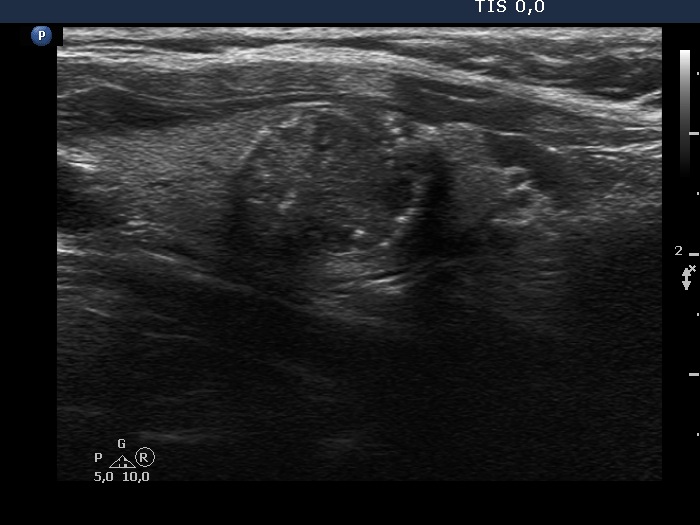

Ultrasonography. The thyroid was echonormal. There was a dominantly hypoechoic nodule in the left lobe. The nodule had both microcalcifications and macrocalcification and was avascular.